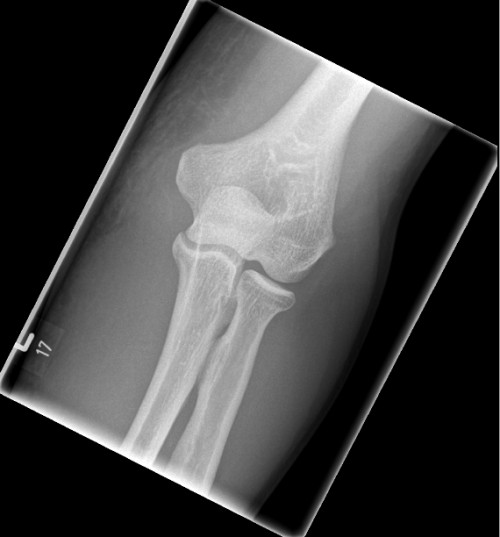

Ein 54 Jahre alter Patient stellt sich bei Ihnen in der Notfallambulanz vor. Er erzählt vor 5 Tagen bei seiner Tätigkeit als Postbote gestolpert und nach hinten gefallen zu sein. Dabei habe er seinen Arm nach hinten geschwungen um sich abzufangen und dabei einen stechenden Schmerz verspürt. Er war bereits am Unfalltag bei einer Kollegin von Ihnen in der Nofallambulanz. Diese hatte eine Schwellung und ein Hämatom am Unter- und Oberarm medialseitig inspektorisch, sowie ein Kraftdefizit beim Heben im Ellenbogen festgestellt. Im daraufhin angefertigten Röntgenbild (siehe unten) wurde keine Fraktur festgestellt. Daraufhin wurde ein Oberarm-Cast angelegt und dem Patienten ein zeitnaher MRT-Termin organisiert. Nun stellt sich der Patient zur Befundbesprechug und Planung des Procedere vor. Nach Abnahme der Gipsschiene sehen Sie folgenden Inspektionsbefund.